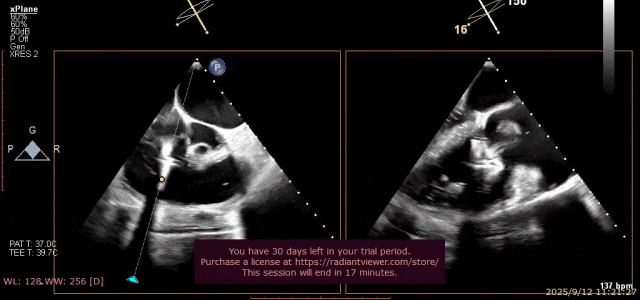

术前3D

手术过程

在超声指导下顺利穿刺房间隔,沿输送系统将NeoNova® C6夹合器送至左房,调整夹合器位置和orientation后进行跨瓣。经确认将C6送达3区,操作捕获瓣叶,确认前后瓣叶充分捕捉后夹闭C6。